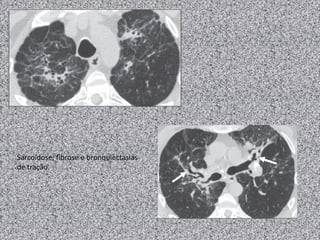

Sarcoidose: fibrose e bronquiectasias

de tração.

Sarcoidose: fibrose ebronquiectasias de tração.